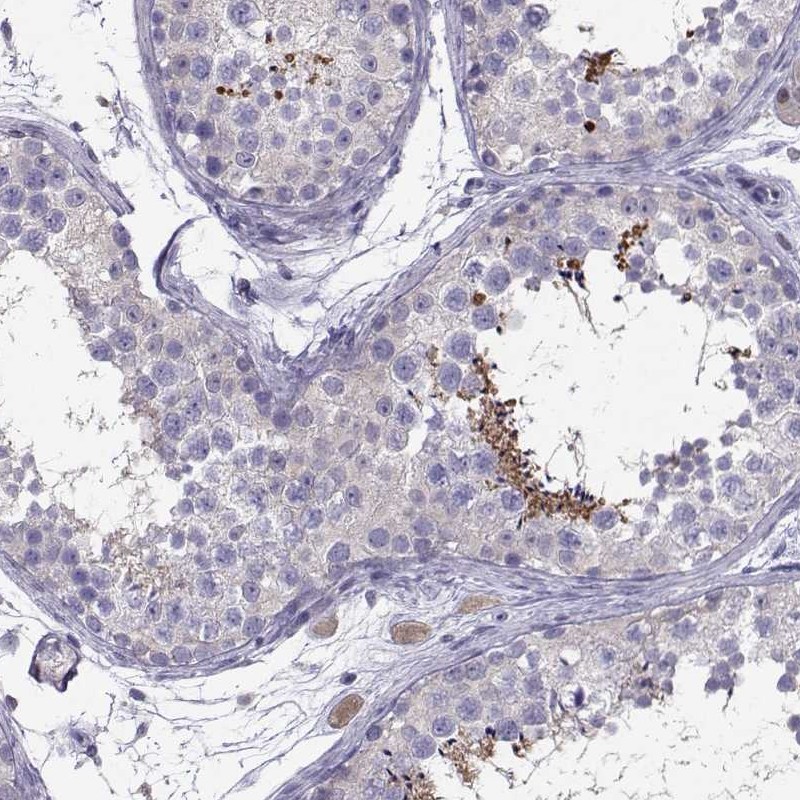

Immunohistochemical staining of human testis shows strong cytoplasmic positivity of a subset of cells in seminiferous ducts.